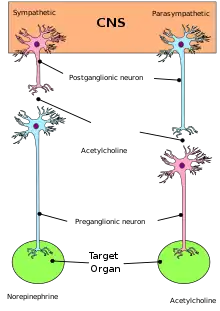

The autonomic nervous system has been classically divided into the sympathetic nervous system and parasympathetic nervous system only (i.e. exclusively motor). The sympathetic division emerges from the spinal cord in the thoracic and lumbar areas, terminating around L2-3. The parasympathetic division has craniosacral "outflow", meaning that the neurons begin at the cranial nerves (specifically the oculomotor nerve, facial nerve, glossopharyngeal nerve and vagus nerve) and sacral (S2-S4) spinal cord.

The autonomic nervous system is unique in that it requires a sequential two-neuron efferent pathway; the preganglionic neuron must first synapse onto a postganglionic neuron before innervating the target organ. The preganglionic, or first, neuron will begin at the "outflow" and will synapse at the postganglionic, or second, neuron's cell body. The postganglionic neuron will then synapse at the target organ.

Motor neurons of the autonomic nervous system are found in "autonomic ganglia". Those of the parasympathetic branch are located close to the target organ whilst the ganglia of the sympathetic branch are located close to the spinal cord.

The sympathetic ganglia here, are found in two chains: the pre-vertebral and pre-aortic chains. The activity of autonomic ganglionic neurons is modulated by "preganglionic neurons" located in the central nervous system. Preganglionic sympathetic neurons are located in the spinal cord, at the thorax and upper lumbar levels. Preganglionic parasympathetic neurons are found in the medulla oblongata where they form visceral motor nuclei; the dorsal motor nucleus of the vagus nerve; the nucleus ambiguus, the salivatory nuclei, and in the sacral region of the spinal cord.

Neurotransmitters

At the effector organs, sympathetic ganglionic neurons release noradrenaline (norepinephrine), along with other cotransmitters such as ATP, to act on adrenergic receptors, with the exception of the sweat glands and the adrenal medulla:

- Acetylcholine is the preganglionic neurotransmitter for both divisions of the ANS, as well as the postganglionic neurotransmitter of parasympathetic neurons. Nerves that release acetylcholine are said to be cholinergic. In the parasympathetic system, ganglionic neurons use acetylcholine as a neurotransmitter to stimulate muscarinic receptors.

- At the adrenal medulla, there is no postsynaptic neuron. Instead, the presynaptic neuron releases acetylcholine to act on nicotinic receptors. Stimulation of the adrenal medulla releases adrenaline (epinephrine) into the bloodstream, which acts on adrenoceptors, thereby indirectly mediating or mimicking sympathetic activity.